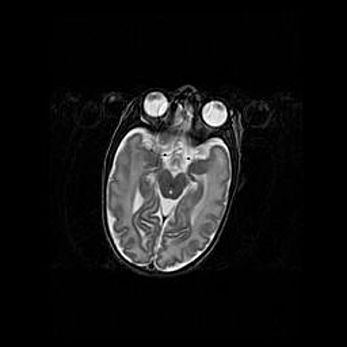

Мальформация Денди-Уокера. Киста задней черепной ямки.

Агенезия мозолистого тела.

Возраст: 2,5 месяца

Вес: 2420 г

Пол: женский

Окружность головы: 37 см

Срок гестации: 32 недели

Мальформация Денди—Уокера — редкий вид патологии ЦНС, представляющий собой врожденный порок развития каудального отдела ствола и червя мозжечка, ведущий к неполному раскрытию срединной (Мажанди) и латеральных (Лушка) апертур IV желудочка мозга. Для этогно синдрома характерна триада симптомов: гипотрофия червя мозжечка и/или полушарий мозжечка, кисты задней черепной ямки, гидроцефалия различной степени. В 70% случаев порок сочетается и с другими аномалиями головного мозга, в частности с агенезией мозолистого тела.